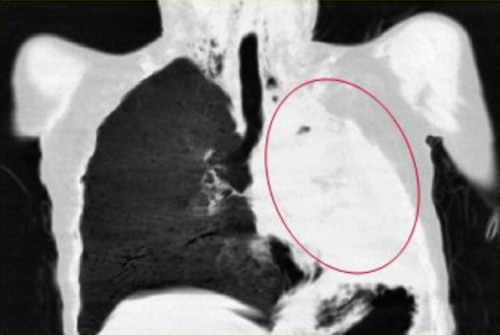

![中医治疗#肺癌# ,是如何一步一步好转的?【门诊案例,仅供参考,不可一概而论,如有问题,须由专业医生问诊之后开方】郑女士 62岁 农民 患者在地里干活时出现胸背部疼痛剧烈,咳嗽,咳痰就赶紧去当地医院就诊行胸椎MRI显示:1.T5/6椎体及其右侧椎弓根异常信号;2.左侧胸腔积液。胸部CT显示:1.左肺门旁占位病变2.纵膈淋巴结多发转移2.双侧胸腔积液3.T5椎体右侧横突、椎弓根及第5、6后肋骨转移。考虑为肺癌骨转移在CT引导下行经皮左肺占位穿刺活检术,术后病理确诊为左肺腺癌。基因检测示:EGFR L858R 突变丰度27%,21因子突变。最终确诊为左肺腺癌;纵膈淋巴结转移,胸腔转移,多发骨转移做了放化疗和吃靶向药之后,患者身体承受不住,当地医院建议,找个好一点的中医调理一下,患者经过病友推荐,找到了我。【症状表现】胸背疼痛,咳嗽,痰少,喘促,痰中带血,乏力气短,面色苍白,纳差,舌淡红,有齿痕,舌苔白,脉细弱。【诊断结果】毒邪蕴结 气血虚弱证【诊治思路】益气补血,解毒抗癌经我开的方子调理之后,患者身体明显好转,胸腰背疼痛,咳嗽,痰中带血,症状消失。复查结果显示患者肺内、纵隔肿瘤,胸腔积液已经基本消失,各项指标均恢复正常,达到临床治愈。目前继续中医药并靶向治疗防止复发。郑女士的身体非常好,已与正常人无异,这样的结果让患者及家属都非常满意,开玩笑说要不是当初的这些片子,病理报告,甚至有些怀疑当初是误诊了呢![你好]我是肿瘤科医生武常生,擅长用中医的方法治疗肺结节、乳腺结节、甲状腺结节、肺癌、乳腺癌、肠癌、宫颈癌、卵巢癌等肿瘤结节问题,并且有多年的临床治疗经验【如果你有肺结节、乳腺结节、甲状腺结节、肺癌、乳腺癌、肠癌、宫颈癌、卵巢癌等结节肿瘤方面的问题,需要我的帮助,可以在评论区打“需要帮助”,帮你辨证分析】](https://wx2.sinaimg.cn/large/008oAFzaly1hlsytz68n3j30b407qdjd.jpg)

中医治疗#肺癌# ,是如何一步一步好转的?【门诊案例,仅供参考,不可一概而论,如有问题,须由专业医生问诊之后开方】郑女士 62岁 农民 患者在地里干活时出现胸背部疼痛剧烈,咳嗽,咳痰就赶紧去当地医院就诊行胸椎MRI显示:1.T5/6椎体及其右侧椎弓根异常信号;2.左侧胸腔积液。胸部CT显示:1.左肺门旁占位病变2.纵膈淋巴结多发转移2.双侧胸腔积液3.T5椎体右侧横突、椎弓根及第5、6后肋骨转移。考虑为肺癌骨转移在CT引导下行经皮左肺占位穿刺活检术,术后病理确诊为左肺腺癌。基因检测示:EGFR L858R 突变丰度27%,21因子突变。最终确诊为左肺腺癌;纵膈淋巴结转移,胸腔转移,多发骨转移做了放化疗和吃靶向药之后,患者身体承受不住,当地医院建议,找个好一点的中医调理一下,患者经过病友推荐,找到了我。【症状表现】胸背疼痛,咳嗽,痰少,喘促,痰中带血,乏力气短,面色苍白,纳差,舌淡红,有齿痕,舌苔白,脉细弱。【诊断结果】毒邪蕴结 气血虚弱证【诊治思路】益气补血,解毒抗癌经我开的方子调理之后,患者身体明显好转,胸腰背疼痛,咳嗽,痰中带血,症状消失。复查结果显示患者肺内、纵隔肿瘤,胸腔积液已经基本消失,各项指标均恢复正常,达到临床治愈。目前继续中医药并靶向治疗防止复发。郑女士的身体非常好,已与正常人无异,这样的结果让患者及家属都非常满意,开玩笑说要不是当初的这些片子,病理报告,甚至有些怀疑当初是误诊了呢![你好]我是肿瘤科医生武常生,擅长用中医的方法治疗肺结节、乳腺结节、甲状腺结节、肺癌、乳腺癌、肠癌、宫颈癌、卵巢癌等肿瘤结节问题,并且有多年的临床治疗经验【如果你有肺结节、乳腺结节、甲状腺结节、肺癌、乳腺癌、肠癌、宫颈癌、卵巢癌等结节肿瘤方面的问题,需要我的帮助,可以在评论区打“需要帮助”,帮你辨证分析】